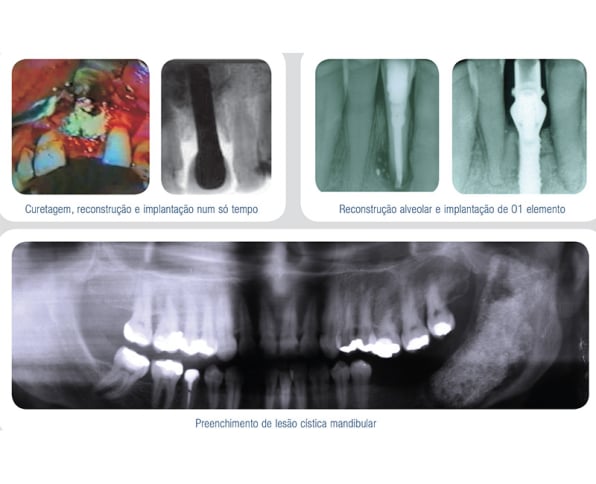

Os produtos OSTEOSYNT vêm sendo cada vez mais utilizados na Implantodontia, nos procedimentos de reconstrução do rebordo alveolar total ou parcialmente perdido, como conseqüência de doenças periodontais, cistos, tumores, traumatismos e consequente perda de elementos e necessidade de sua substituição.

Veja abaixo alguns casos já tratados com as biossoluções EincoBio com resultados de sucesso:

- Curetagem e reconstrução em área de abcesso;

- Curetagem, reconstrução e implante em um só tempo;

- Reconstrução alveolar de 01 elemento;